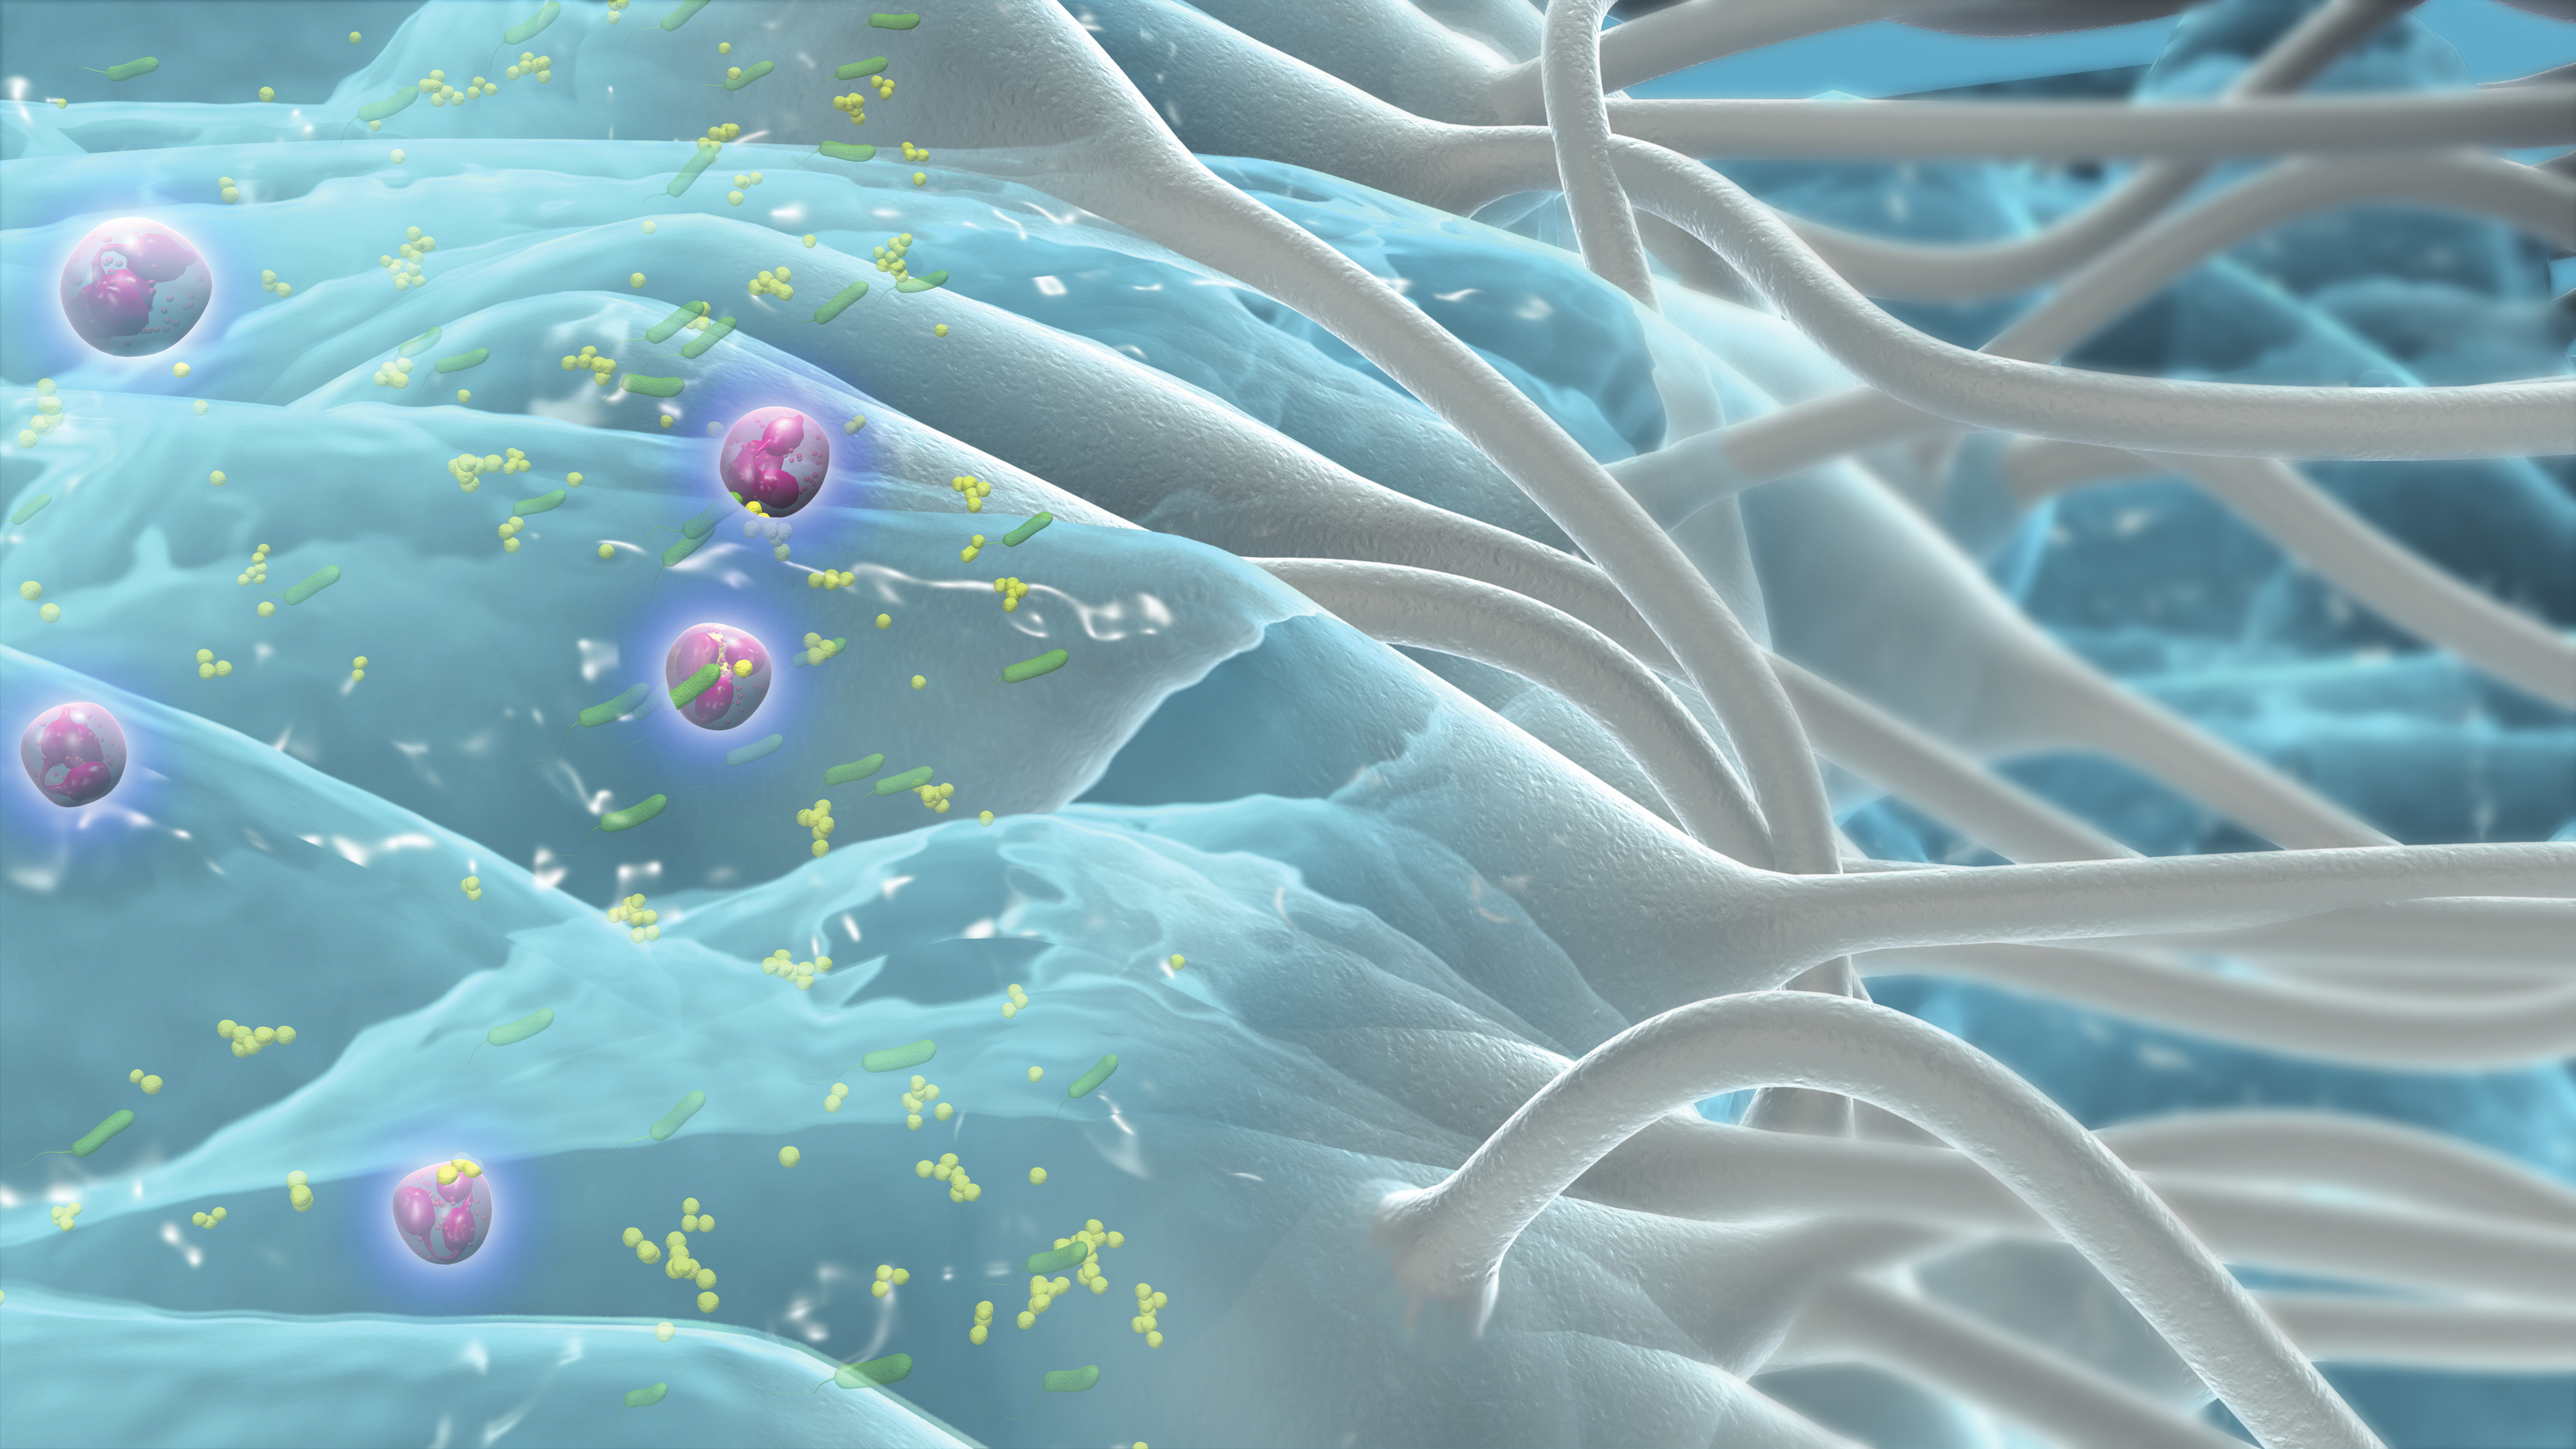

Låser in sårvätska och fångar bakterier*1-3

Kan bidra till att minimera sårinfektion och korsinfektion vid borttagning6,7

Mikrokonturer till sårbädden*8